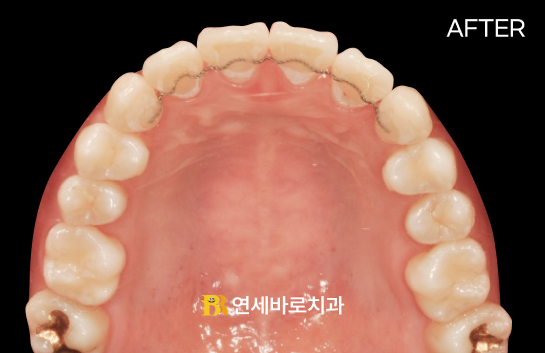

[앞니가 깊게 물린 과개교합 케이스] 아랫니가 완전히 가려진 상태에서 비발치 교정으로 가지런한 배열과 교합을 완성시켰습니다